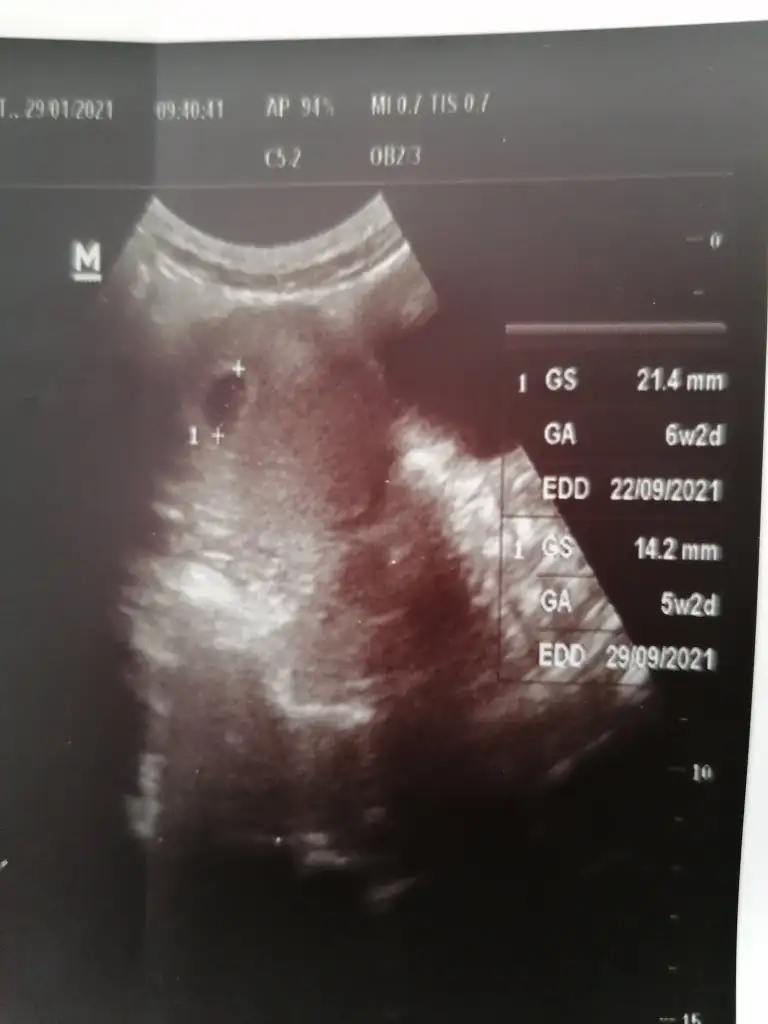

Kızlar devlete kan testleri için gittim doktor: özelde ki doktorları anlamıyorum, kalp duymadan ben yaptırmam kan testi.. dedi ve ultrasona soktu duymadı kalp neyim..şimdi bilgili canım yoldaşlarım bebek var di mi kesede şu yanda yazılanlarda gs mi boyutu.. Kan testlerim kaldı mecbur özelde yaptırcam kalanları bir daha işten zor izin alırım.

Eklentiler

• IMG_20210129_100804.webp

17,6 KB · Görüntüleme: 100

Ama şimdi jetonum düştü kese boyutu olması gerekenden küçük ve hafta bir hafta geride yanlış mı anlıyorum acaba çok canım sıkıldı.

Bana da kalp atışını duyunca yazalım kanları dedi dr ve benimki de bir hafta geri gibi suan. Kesenin ici bombos hicbisey yok. Yumurtlama gününü biliyomusun?